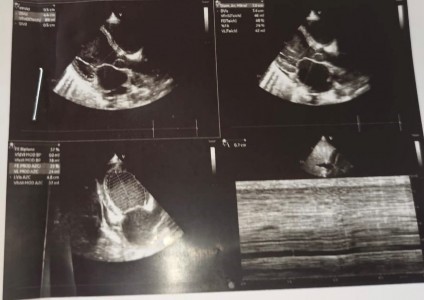

En el ecocardiograma se evidenció disfunción sistólica ventricular izquierda, con FEVI 39 %. Dímero D = 6,98 ug/mL, ferritina = 522 ng/mL, BT= 1,72, TGO = 49, TGP = 30, Cr = 0,47, CPK MB = 12,20. Por ello, se indicó tratamiento con captopril 6,25 mg vía oral cada doce horas más carvedilol 3,125 mg vía oral cada 12 horas y continuó su tratamiento con diuréticos. Finalmente, fue dado de alta afebril, sin edemas y con resolución de la falla hepática y del trastorno de coagulación (Figura 2 y Figura 3).